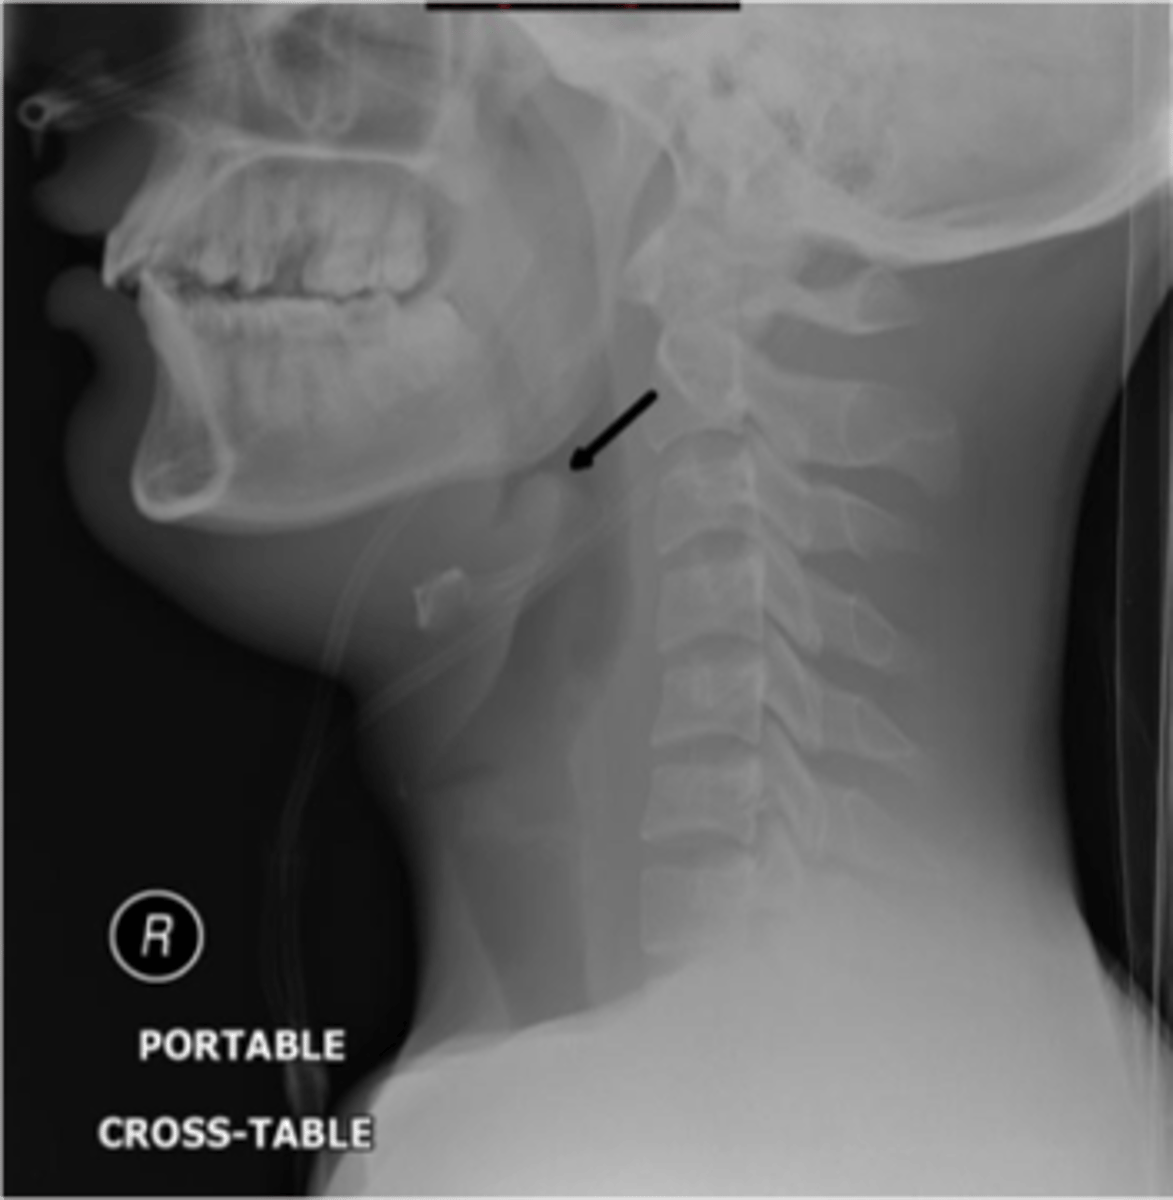

Epiglottitis (thumb sign)